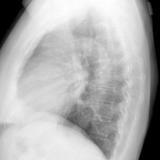

Peric stripe - slightly thickened

close up

Date: 03/17/2004

Views: 3834